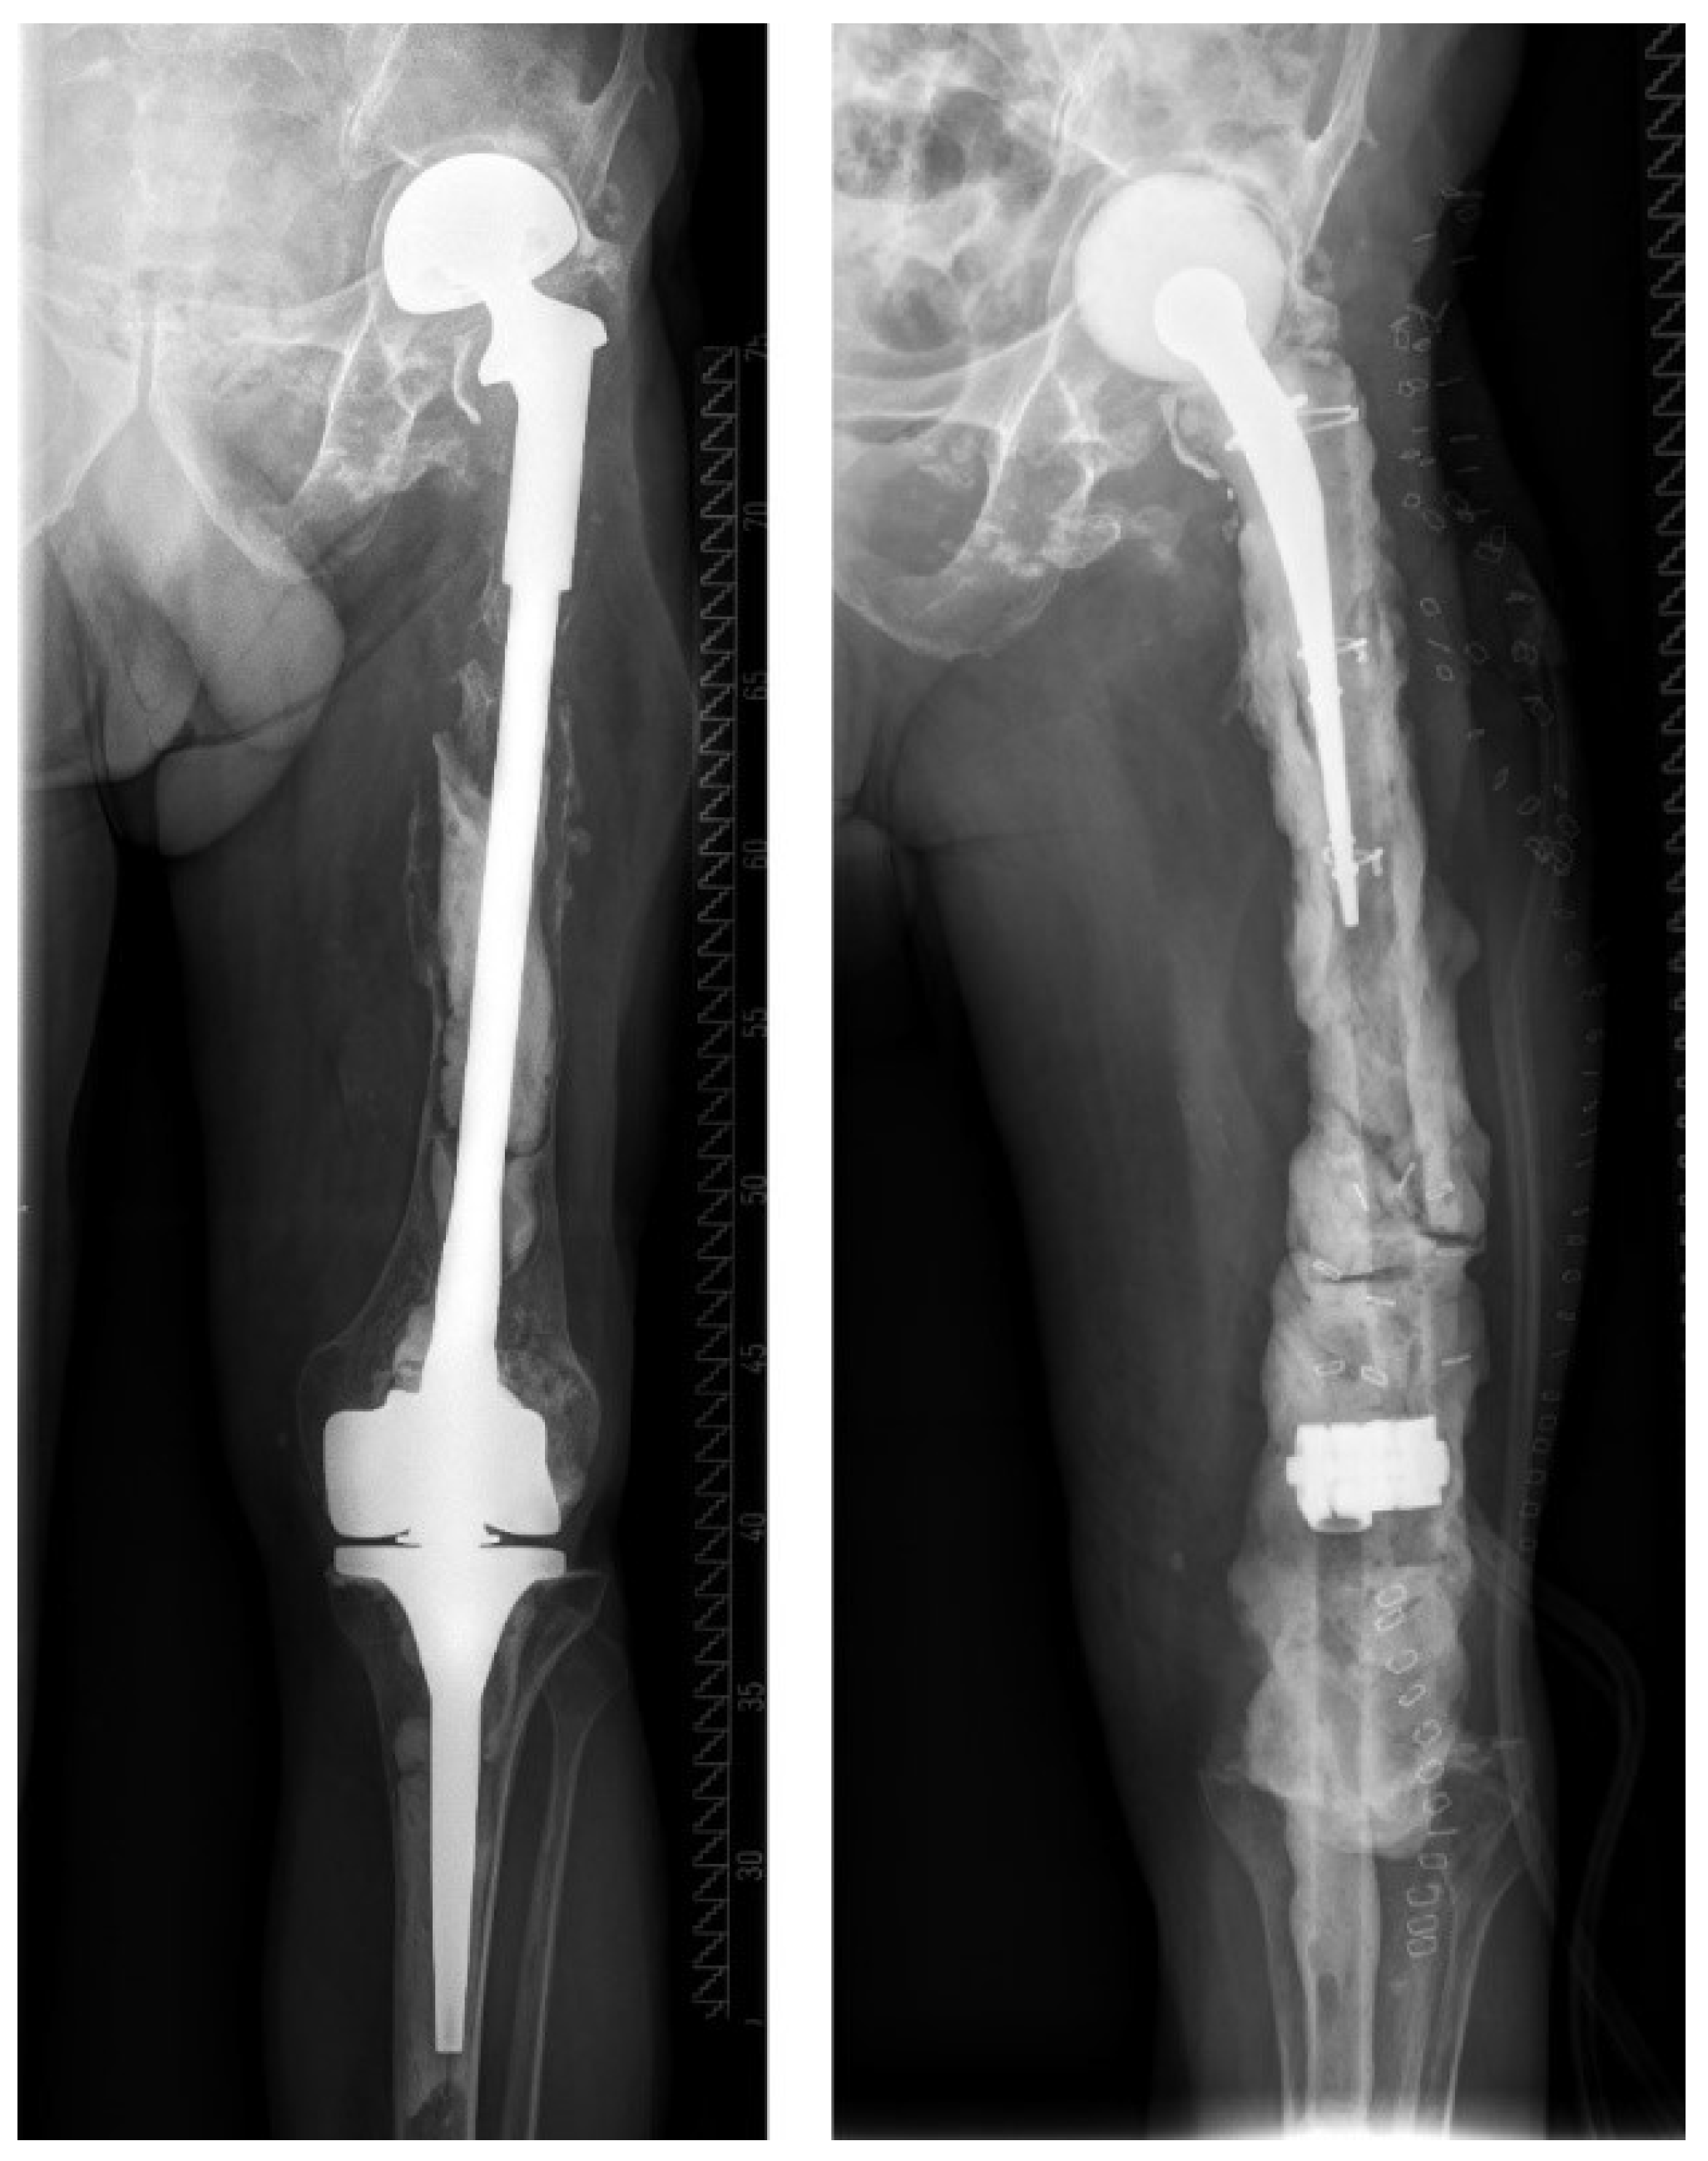

| T | T0 | a | Stable standard implant without important soft tissue defect |

| b | Stable revision implant without important soft tissue defect | ||

| T1 | a | Loosened standard implant without important soft tissue defect | |

| b | Loosened revision implant without important soft tissue defect | ||

| T2 | a | Severe soft tissue defect with standard implant | |

| b | Severe soft tissue defect with revision implant | ||